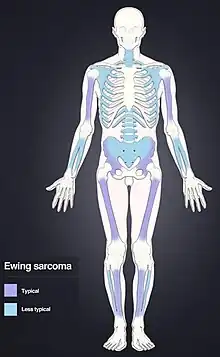

Ewing sarcoma (EwS) is a type of cancer that can form in bone or in soft tissue.[1] Symptoms may include swelling and pain at the site of the tumor, fever, or a bone fracture.[3] The most common areas affected are the shafts of long bones of the legs, the pelvis, and the chest wall.[5] In soft tissue, it can affect various parts of the body.[6] In about 25% of cases, the cancer has already spread to other parts of the body at the time of diagnosis.[7]

It can occur anywhere in the body, but most commonly in the pelvis and the long tubular bones, especially around the growth plates.[1] The diaphyses of the thigh bone are the most common sites, followed by the tibia and the upper arm bone. Around 25% have spread at presentation.[1] In soft tissue, it can affect a wide distribution of the body.[6] Rarely, it can develop in the cervix, vagina and vulva.[10]